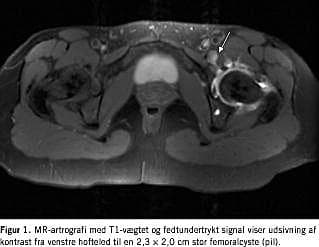

En 33-årig kvinde blev henvist til vurdering af en udfyldning i venstre lyske. Patienten havde haft symptomer i fire år med smerter ned på for- og medialsiden af venstre femur, specielt ved fysisk anstrengelse. En ultralydskanning viste en 2,5 × 2,5 × 3,7 cm stor cyste distalt for ligamentum inguinale medialt for vena femoralis med tegn på forbindelse op under ligamentet, og konklusionen var femoralhernie. Ved eksploration af lysken fandt man en femoralcyste på 5 × 5 cm distalt for ligamentum inguinale strækkende sig ned til bunden af karskeden. Cysten blev excideret og histologien viste en mesotelcyste uden malignitet. Få måneder efter operationen recidiverede symptomerne fra lysken. En ny ultralydskanning viste normale forhold, men ved efterfølgende MR-skanning fandt man recidiv i form af en 2 cm stor cyste. Ved ortopædkirurgisk vurdering blev der påvist let springhofte og knækkelyde fra hoften. For at verificere en mulig forbindelse til hoften forsøgte man ultralydvejledt fistulografi ved punktur af cysten, men teknisk uden held. Herefter foretog man under røntgengennemlysning punktur af hofteleddet og injicerede 20 ml NaCl med 0,4 ml gadolineum 0,5 mg/ml. En efterfølgende MR-artrografi med aksiale, parakoroneale og sagittale T1-vægtede sekvenser med fedtundertrykt signal viste normale forhold i hofteleddet og udsivning af kontrast langs muskelfibrene samt en diskret bræmme af kontrast i den 2,3 × 2,0 cm store femoralcyste. Efter at patienten havde været oppegående i knap en time, gentog man MR-skanningen og fik nu verificeret en fistel fra hofteleddet til femoralcysten (Figur 1 ). Hofteleddet blev artroskoperet gennem anterior adgang og man fandt fovea centralis helt dækket med fibrose og ligamentum teres revet fra og slået ind i leddet. Man lokaliserede den ved MR-artrografi påviste fistel beliggende proksimalt og anteriort under labrum. Fistelåbningen i ledkapslen blev lukket med to suturankre placeret i acetabulum, således at defekten i ledkapslen blev trukket ned til acetabulum. Postoperativ genoptræning førte til normalt funktionsniveau.

Ved fundet af en udfyldning i lysken, hvor man ikke umiddelbart formoder, at der er et hernie, er en grundig anamnese og detaljeret objektiv undersøgelse essentiel for at tilrettelægge et sufficient udredningsprogram. Ultralydskanning er førstevalg med specificitet over for hernie på op til 96% [4], afhængig af radiologens erfaring. Ved Doppler-ultralydskanning kan man klarlægge mulig relation til karrene. Ved mistanke om forbindelse til naboorganer, f.eks. hoften, symfysen [5], intraperitonealt eller retroperitonealt, kan der suppleres med MR-skanning evt. med artrografi. MR-artrografi viste i dette tilfælde sin force til verificering af forbindelsen til hofteleddet.